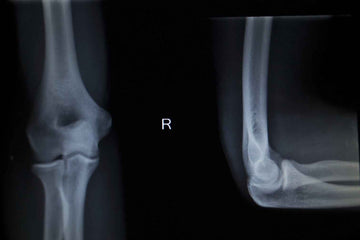

In tennis elbow sufferers the muscles and tendons of the forearm become damaged from overuse, which leads to pain and tenderness on the outside of the elbow.

You feel pain on the outer part of the elbow and the bone on the outside of the elbow feels tender. You might feel pain from gripping and movements of the wrist. Your wrist hurts from movements such as pouring a jug of liquid, lifting with the palm down or sweeping.